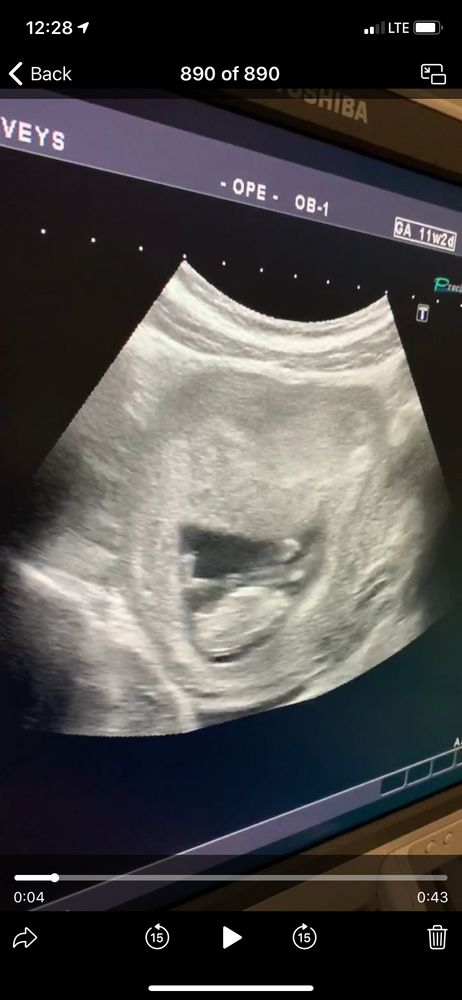

УЗИ, КТГ, доплер11 недель + 3 дня . На кого больше похоже?🙈 если, конечно , можно рассмотреть)

Аппарат на котором сделано фото, не такого качества, чтобы определить на таком раннем сроке пол.

На первом фото похоже на мальчика, у меня в этот раз такой же был в 11 недель)

Я бы сказала вероятность девочки 50/50 😄 А вообще я делала скрининг на Вашем сроке, потом переделывала узи в 13 недель из-за проблем, вот в 13 недель бугорок уже был хорошо поднят вверх, сомнений оставалось мало, если будете делать позже узи там будет яснее, бугорок либо поднимется, либо останется прямой))

На таком сроке половой бугорок выглядит одинаково у девочек и мальчиков, только небольшая разность угла наклона и не на 100% может указывать на пол, но только на хорошем аппарате и опытный узист🤷♀️